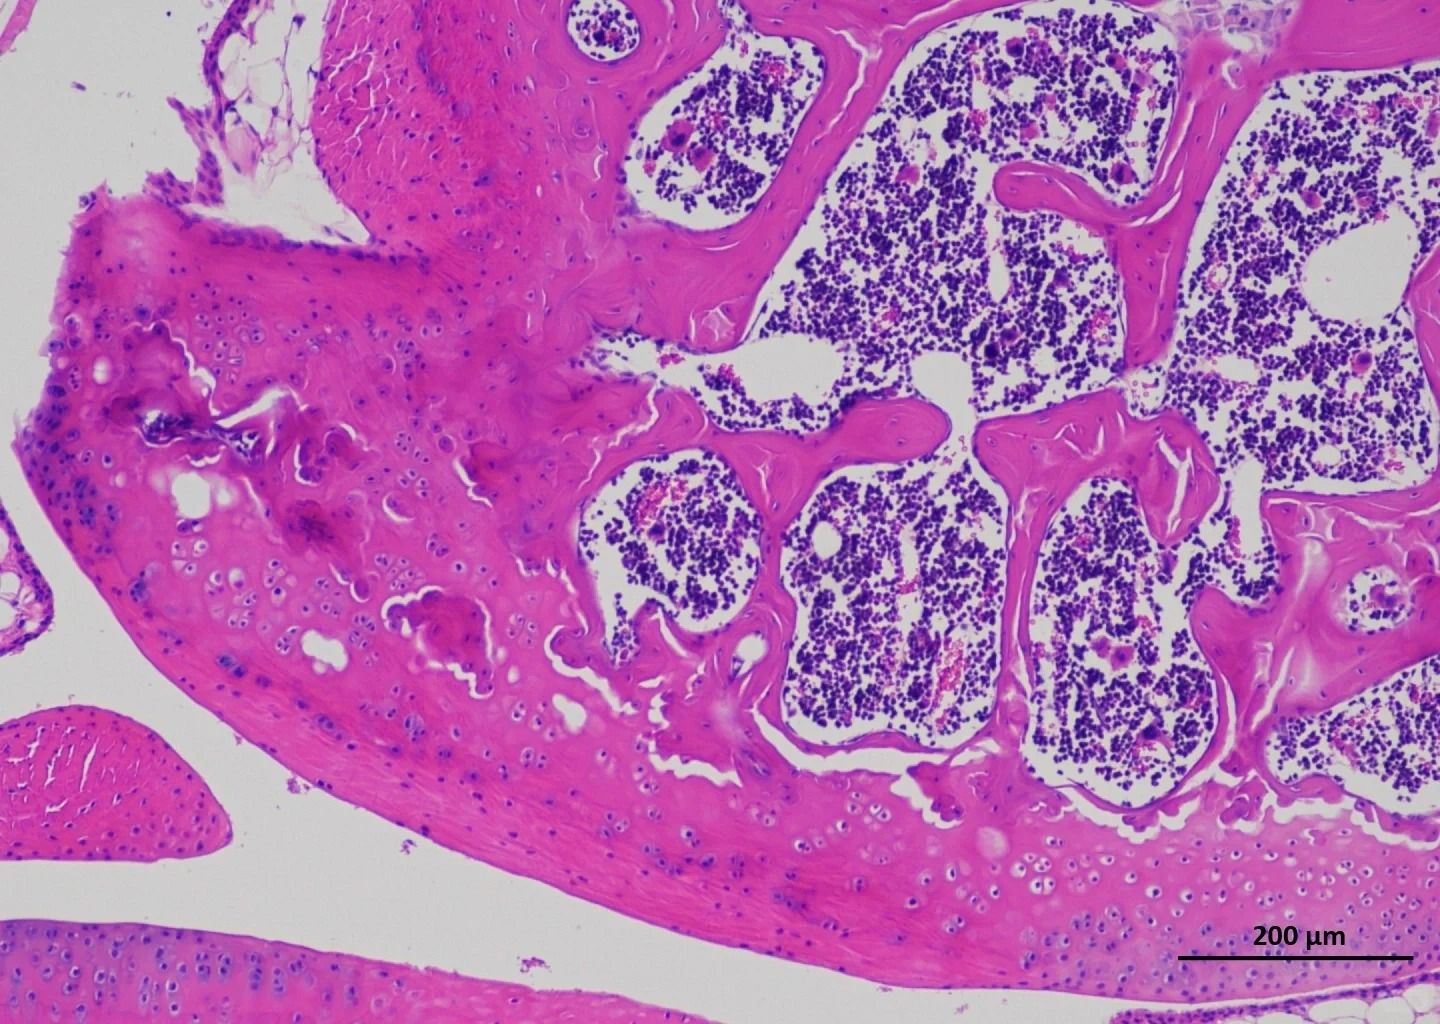

普拉特澤生物承接甲苯胺藍染色等病理染色相關(guān)服務上萬例,積累了操作大量經(jīng)驗,為大家推薦分享甲苯胺藍染色試劑盒

適用場景:常規(guī)組織切片染色(如軟骨、肥大細胞、植物細胞壁等)。

特點:提供預配染色液,支持多種染色方案(如神經(jīng)組織、肥大細胞特異性染色)。

適用場景:病理學、細胞生物學研究。

●肥大細胞染色:甲苯胺藍可異染性顯示顆粒,需嚴格控制pH值(酸性條件)。